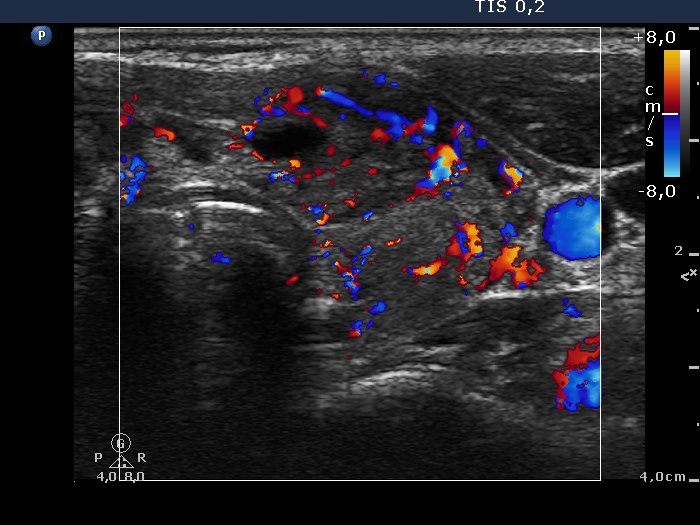

Case 974 (ultrasonographic picture 8)

Lower part of the left lobe, longitudinal scan. The vascularity is increased.